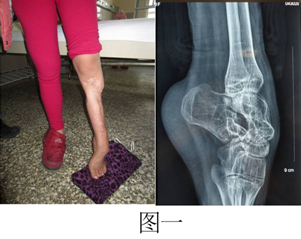

病例一:患者女,13岁,因“左足外伤术后内翻畸形伴下肢短缩五年”入院。检查患者左小腿瘢痕挛缩,左踝关节僵硬,左足下垂内翻畸形,下肢短缩5cm(图一)。应用Ilizarov技术在胫骨截骨的基础上缓慢牵伸延长骨段,恢复肢体正常的长度,同时矫正足下垂(图二),是一期手术解决了两个不同的问题,节省病人的花费,取得满意的效果。患者拆除环形外固定架后肢体恢复长度和矫正马蹄足的体表情况(图三)。

术前(图一)